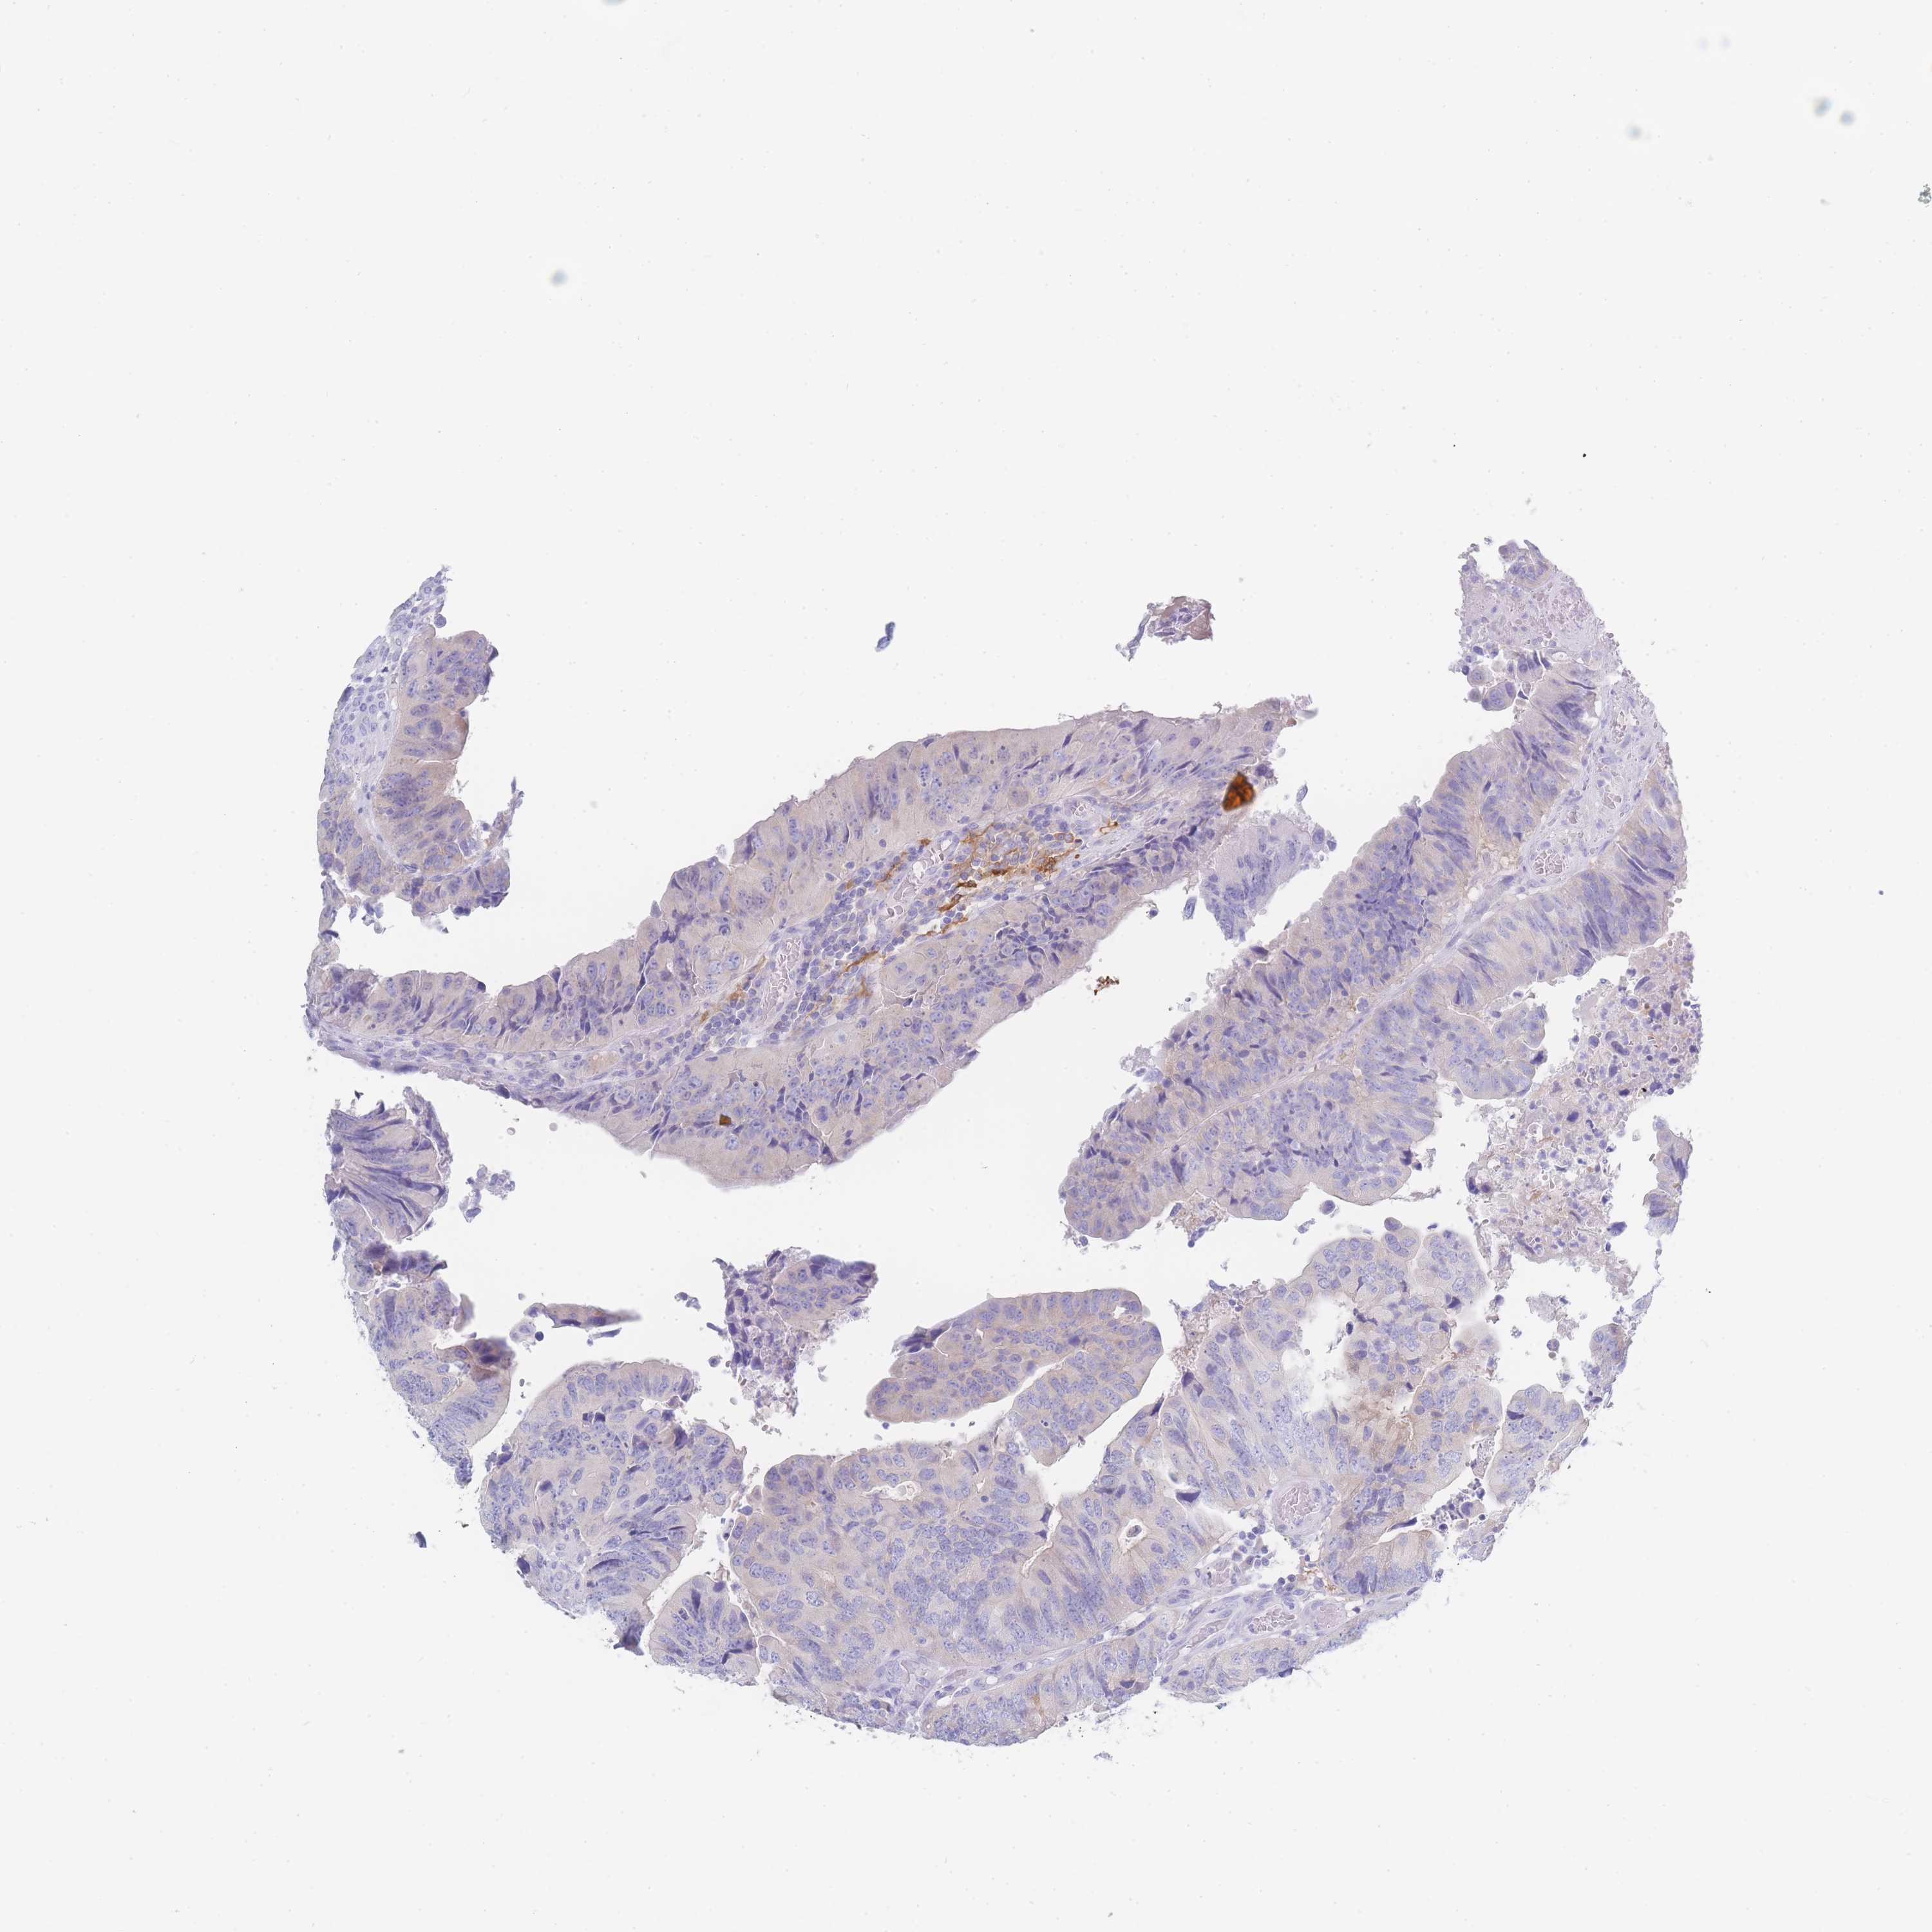

CANCER COLORECTAL CANCER Show tissue menu

Colorectal cancer

Human cancer

Colon adenocarcinoma